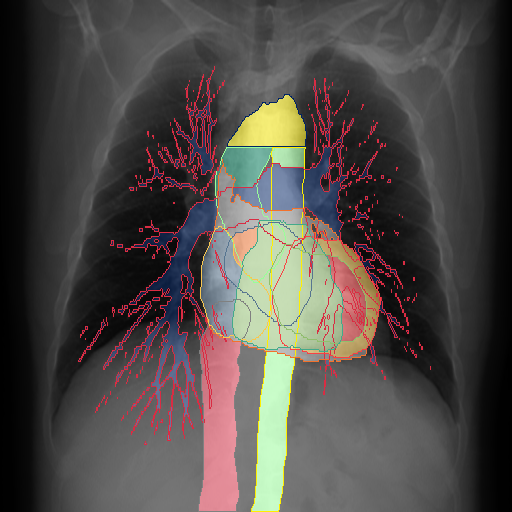

We show qualitative results for frontal projections in Fig. 2. We show a subset of classes belonging to the supercategories lungs, vascular systems, bones, and abdomen/digestive system. The predictions show minor deviations at the boundaries of the individual classes of the respiratory and vasculature system, while some inaccuracies become visible in the abdominal area. The qualitative results for the lateral projections are displayed in Fig. 2. Akin to the frontal view, the predictions show smoother borders but align with the ground truth. Apart from this, the segmentations provide matching insights on the thoracic anatomy with a slight deviation from the ground truth for both frontal and lateral views.

We display qualitative results in Fig. 3. The annotators tend to be content with most annotations. There are edits at the extensions of the esophagus, trachea, and aorta and corrections of the lower ribs. There is little consensus for classes in the abdominal area, such as the stomach, as seen on the right of Fig. 3 . In contrast, the annotators often align for bone classes.